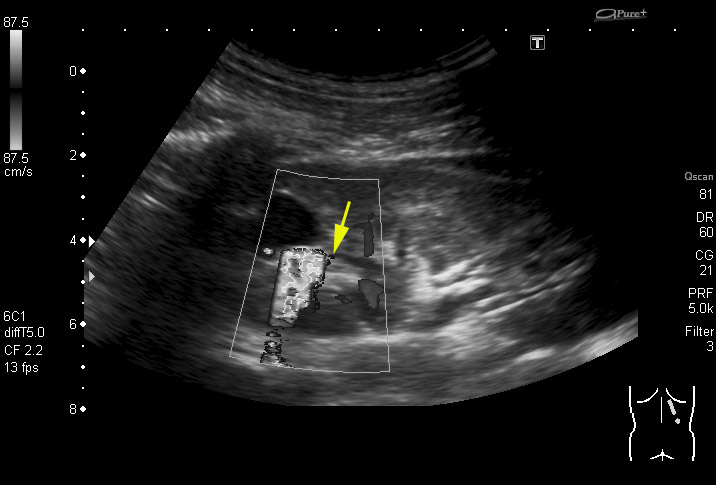

Артефакт цветного твинклинга

Ролик с ЦДК

Для меня самое интересное находится здесь:

Нет, меня интересует "или".dok69 писал(а):Вас занимает артефакт- "мерцания" или ...?

Мальчика выписали без рентгенологического исследования. Будем обходиться УЗИ. Почему это не может быть кистой с конкрементами? Формирование конкрементов в кисте менее вероятно, чем в дивертикуле чашечки или в расширенной чашечке при синроме Фрейли. Но полость уж больно круглая, да и связи с ЧЛС и конфликта с интраренальным сосудом сколько не смотрел, я не увидел.